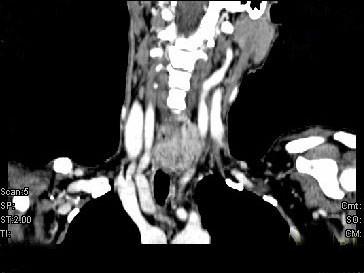

问题 女,50岁,左下颈部扪及一质硬、表面高低不平的包块,肿块逐渐增大,现感吞咽困难,CT如图所示,最可能诊断为()

选项 A.甲状腺癌 B.食管癌 C.喉癌 D.甲状腺原发淋巴瘤 E.颈部神经鞘瘤

答案 A